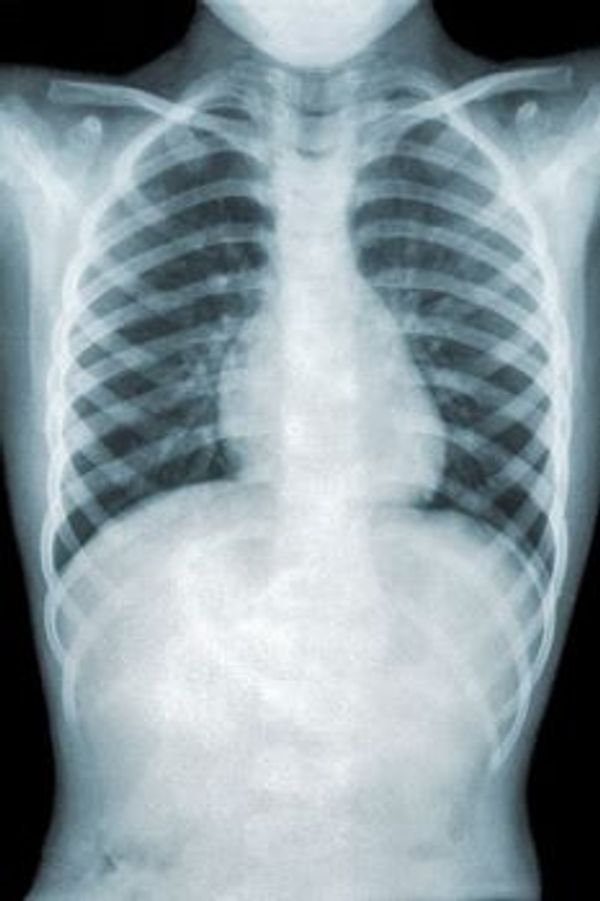

Im Allgemeinen verursacht Mycoplasma pneumoniae ein leichtes, grippeähnliches Krankheitsbild mit viel Husten und leichtem Unwohlsein. In der Regel hat eine Person kein Fieber, aber manchmal treten Muskel- und Kopfschmerzen auf. Die Symptome treten in der Regel allmählich über mehrere Tage bis zu einer Woche auf. Dies steht im Gegensatz z. B. zur Influenza (Grippe), deren Symptome oft sehr akut auftreten. Die Inkubationszeit kann zwischen einer und drei Wochen betragen. Manchmal verläuft die Infektion jedoch schwer und entwickelt sich zu einer Lungenentzündung mit lang anhaltendem Husten. Diese Lungenentzündung wird auch als atypische Lungenentzündung bezeichnet, was bedeutet, dass sie sich anders äußert als eine "normale" Lungenentzündung. Wenn Sie sich mit diesem Bakterium infiziert haben, kann es zu einem späteren Zeitpunkt zu einer erneuten Infektion mit diesem Bakterium kommen.